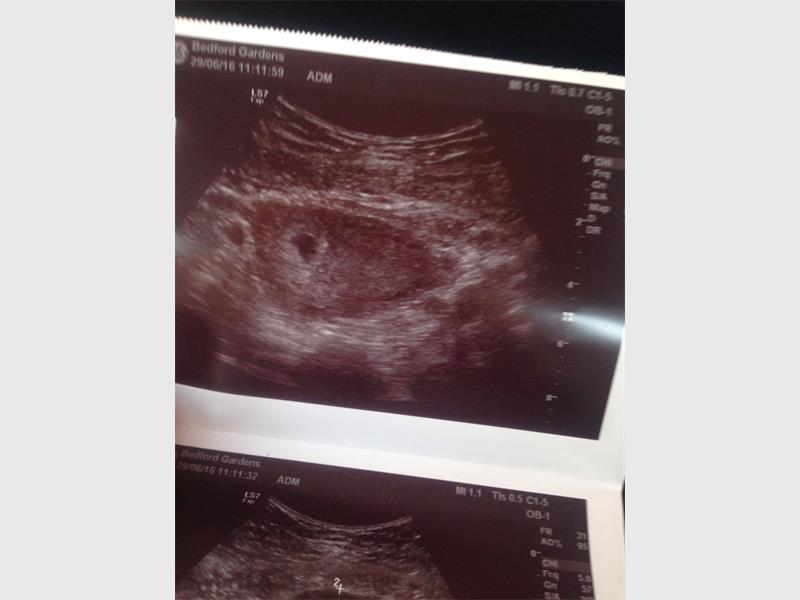

Nicole said she is between five to six weeks pregnant and this time she will visit her doctor more regularly. She is also drinking blood thinners and hormone pills to ensure a safe and healthy pregnancy.